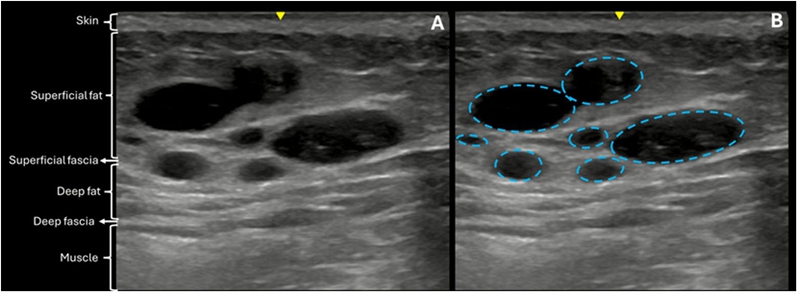

Standardized 2D and 3D imaging demonstrated a clear increase in buttock volume and improvement in overall contour. Common aesthetic concerns, including hip dips and deep infragluteal folds, showed visible correction. Ultrasound imaging confirmed accurate placement of the filler within the subcutaneous layer. Over time, the injected HA gradually integrated with surrounding adipose tissue and underwent partial resorption, without evidence of migration, nodule formation, or fibrosis.

Figure 8–10 | Ultrasound evolution of hyaluronic acid filler over time. Immediate post-treatment images show well-defined, anechoic filler deposits in the subcutaneous layer. At one month, surrounding tissue demonstrates expected reactive changes consistent with early integration. At one year, blurred margins and reduced echogenic contrast indicate partial resorption and incorporation into native tissue, correlating with sustained contour support.